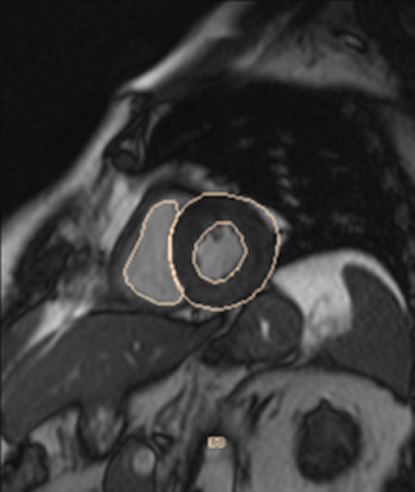

RM Cardíaca

Descripción

Es una prueba diagnóstica no invasiva que obtiene información morfológica y funcional del corazón y las estructuras adyacentes; de esta manera se pueden diagnosticar diferentes patologías congénitas y adquiridas, o bien realizar controles en pacientes con patología previa ya conocida. En la gran mayoría de casos es necesario el uso de contraste intravenoso (gadolinio) para completar el estudio, un tipo de contraste que raramente produce reacciones adversas. Durante la prueba, el técnico le pedirá varias veces que aguante la respiración durante 10-15 segundos para obtener las imágenes lo más claras posible. No se necesita preparación previa alguna por parte del paciente. La duración de la prueba es de aproximadamente 45-60 minutos. Está contraindicada en pacientes con marcapasos; el paciente debe avisar si es portador de implantes metálicos y/o clips quirúrgicos.